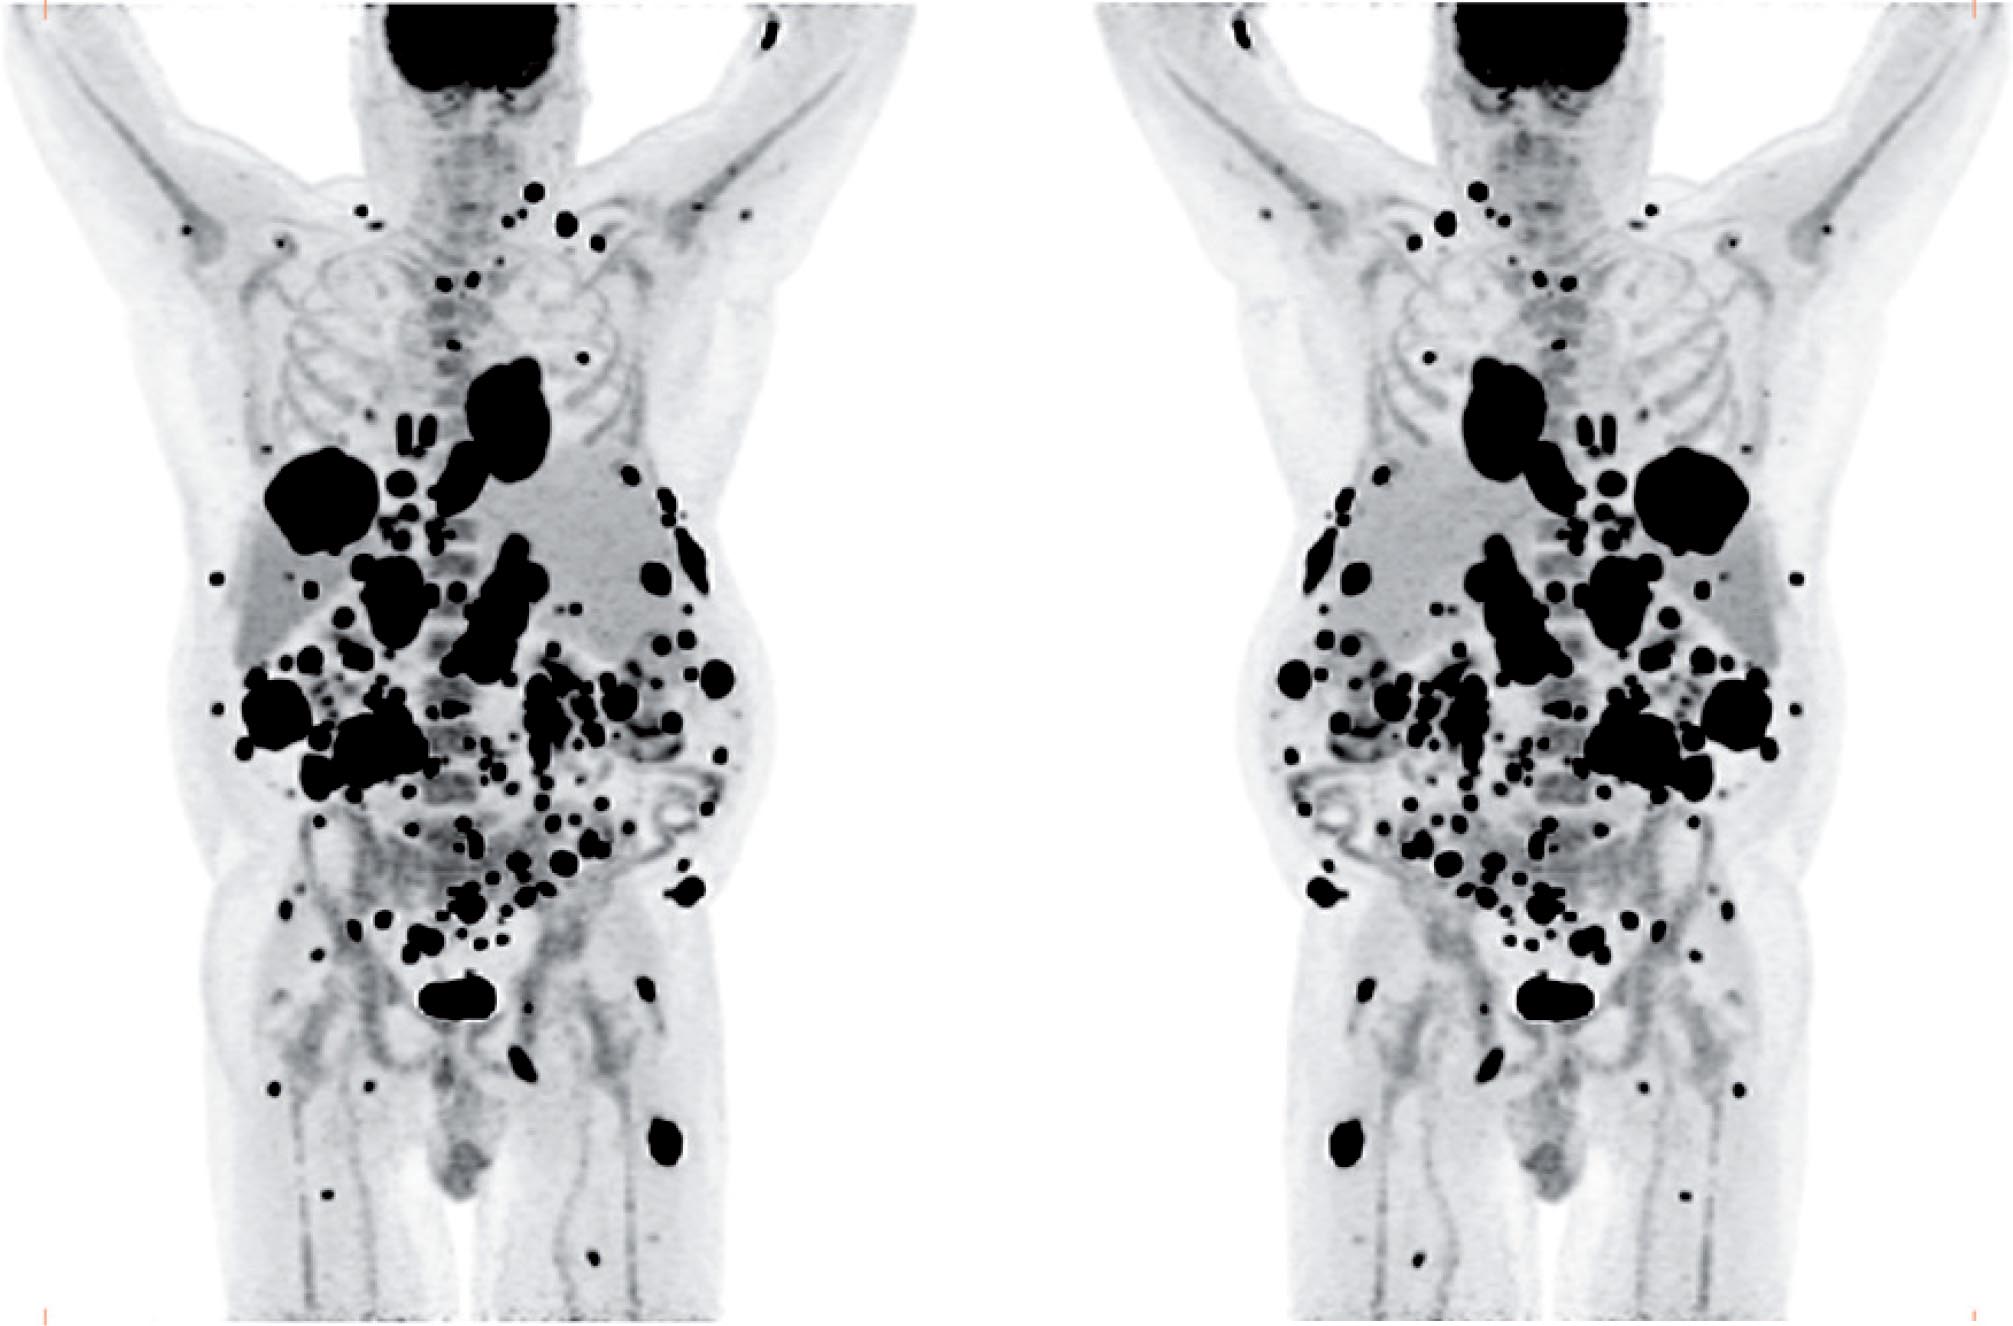

The patient was referred for 18F-FDG-PET/CT the next day to further evaluate the disease extent. A whole-body PET/CT was performed 60 min after the intravenous injection of 629 MBq (17 mCi) 18F-FDG. The study showed multiple hypermetabolic foci throughout the body (Figure 1). There was a large soft tissue mass in the right lower lobe with increased 18F-FDG uptake; the maximum standardized uptake value (SUVmax) of this lesion was 38.0. Also, there were multiple hypermetabolic nodules in the thyroid, gastric mucosa, pancreas, and both the adrenals. Both kidneys contained exophytic lesions with increased 18F-FDG uptake (Figure 2). A circumferential soft tissue mass in the esophagus was hypermetabolic as well. Additional FDG-avid nodules and masses were also found in the peritoneum and omentum; the largest of these had a SUVmax of 68.0. Intense FDG uptake was observed in multiple subcutaneous and intramuscular nodules throughout the body, some of which were thought to represent lymph nodes. Brain magnetic resonance imaging was performed on the same day, which revealed five metastatic lesions measuring up to 1.5 cm in the left frontal lobe, anterior right parietal lobe, and right temporal lobe. At this point, there were multiple candidate lesions for the primary malignancy, such as lung, esophagus, melanoma, or an aggressive lymphoma.

Fig 1

Figure 1. Maximum intensity projection (MIP) images in anterior and posterior views of the 18F-FDG PET/CT images showing multiple hypermetabolic foci of increased FDG uptake throughout the body, most likely representing widespread metastatic disease.

In all three prior reports, 18F-FDG-PET/CT was performed after nephrectomy to evaluate recurrent/metastatic disease and, therefore, evaluation of primary sRCC was not possible. Our patient had metastatic disease of unknown primary origin at the time of the PET/CT study. After the final diagnosis of sRCC, the renal lesions were recognized retrospectively as multiple hypermetabolic exophytic lesions bilaterally, with high 18F-FDG uptake relative to that of normal renal parenchyma. The findings in our patient also demonstrate the high 18F-FDG avidity of sRCC metastatic lesions, consistent with the findings of the three previously reported cases.